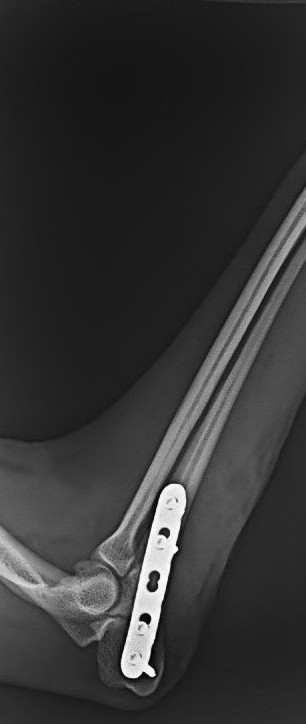

・骨折手術(プレート固定など)

・橈尺骨(前肢)骨折整復術 45万円前後